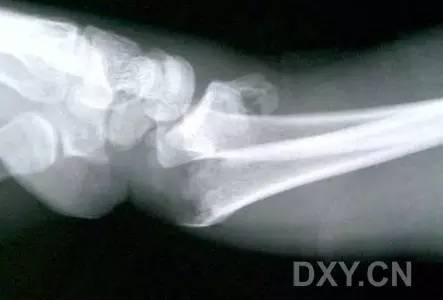

3. Smith 骨折

桡骨远端骨折伴骨折远端向掌侧移位,也称为反 Colles 骨折。

来源:radiology assistant